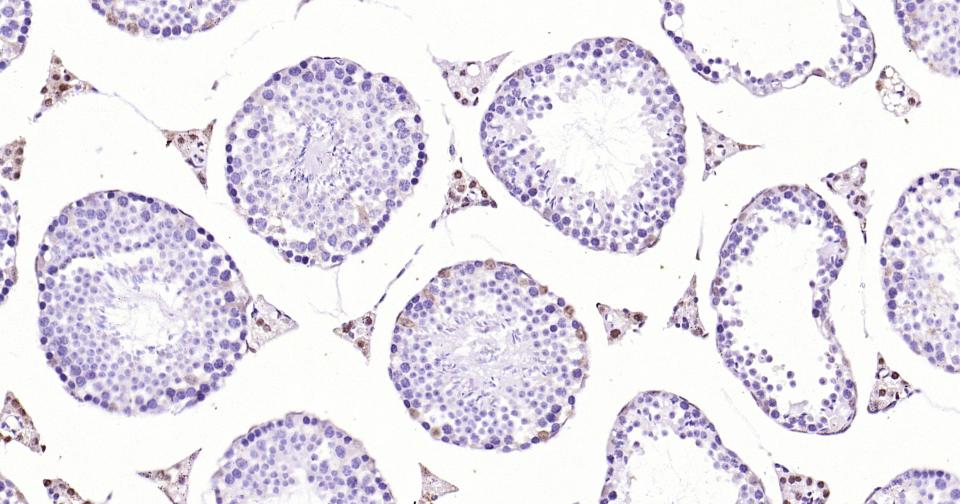

Paraformaldehyde-fixed, paraffin embedded Rat Testicles; Antigen retrieval by boiling in sodium citrate buffer (pH6.0) for 15 min; Antibody incubation with Androgen receptor Monoclonal Antibody, Unconjugated(bsm-61204R) at 1:200 overnight at 4°C, followed by conjugation to the SP Kit (Rabbit, SP-0023)and DAB (C-0010) staining.